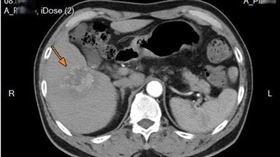

63歲男罹淋巴癌+肝癌 做1事「變小了」

新竹臺大分院收治一名63歲男性,原本罹患淋巴癌,在治...